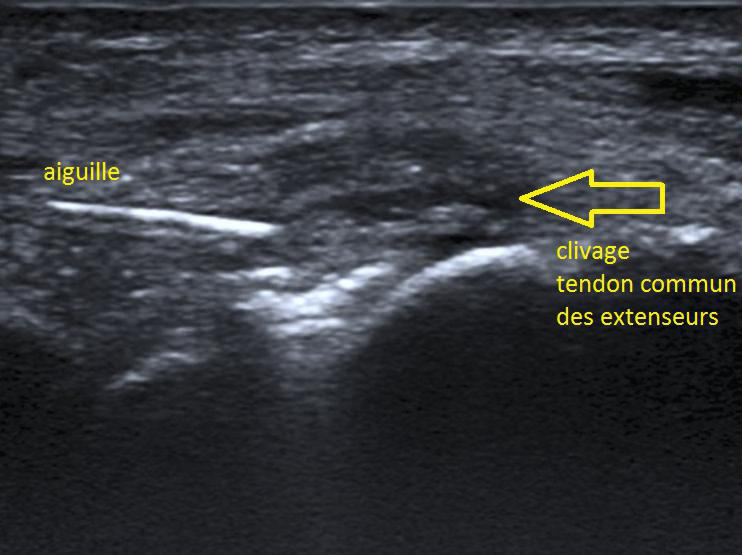

Fenestration – ténonotomie échoguidée – needling

Ces trois expressions sont synonymes. Il s’agit d’une intervention de microperforation des tendons lors de tendinopathies chroniques. Ce traitement a pour but d’induire une réaction cicatricielle dans le tendon, dans un but de réparation. Le geste se fait sous anesthésie locale.

Une fenêtre de 3 mois sans traitement cortisonée est nécessaire, les AINS doivent être stoppés 15 jours avant et après l’intervention. Pendant 4 semaines après l’intervention seule une activité physique normale est autorisée. Une prise en charge de physiothérapie est initiée dès le 15ème jour avec surtout des exercices de renforcement.

Une genouillère peut occasionnellement être utilisée pour les interventions sur le tendon rotulien et une botte de marche pour les interventions sur le tendon d’Achille, mais le plus souvent on permet une mobilisation douce des articulations sans attelle. Nous réalisons ces fenestrations surtout lors d'épicondylite mais également lors d'aponévropathie plantaire, de jumper's knee, de tendinopathie des fessiers et des ischiojambiers.

L'injection de PRP est réalisée sous contrôle échographique avec un matériel de dernière génération (Toshiba Aplio 500) et des sondes linéaires de haute fréquence adaptées à la pratique de la radiologie interventionnelle.

Une anesthésie locale peut être réalisée mais n'est pas obligatoire. Par contre, le produit anesthésiant ne doit pas être mélangé ou injecté à proximité des facteurs plaquettaires (risque d'inhibition) et doit se faire en périphérie du tendon. Ensuite, l'aiguille est placée au sein de la fissure. Le PRP est injecté sous contrôle échographique. Les consignes d'usage habituelles (repos, surveillance) sont ensuite données au patient.